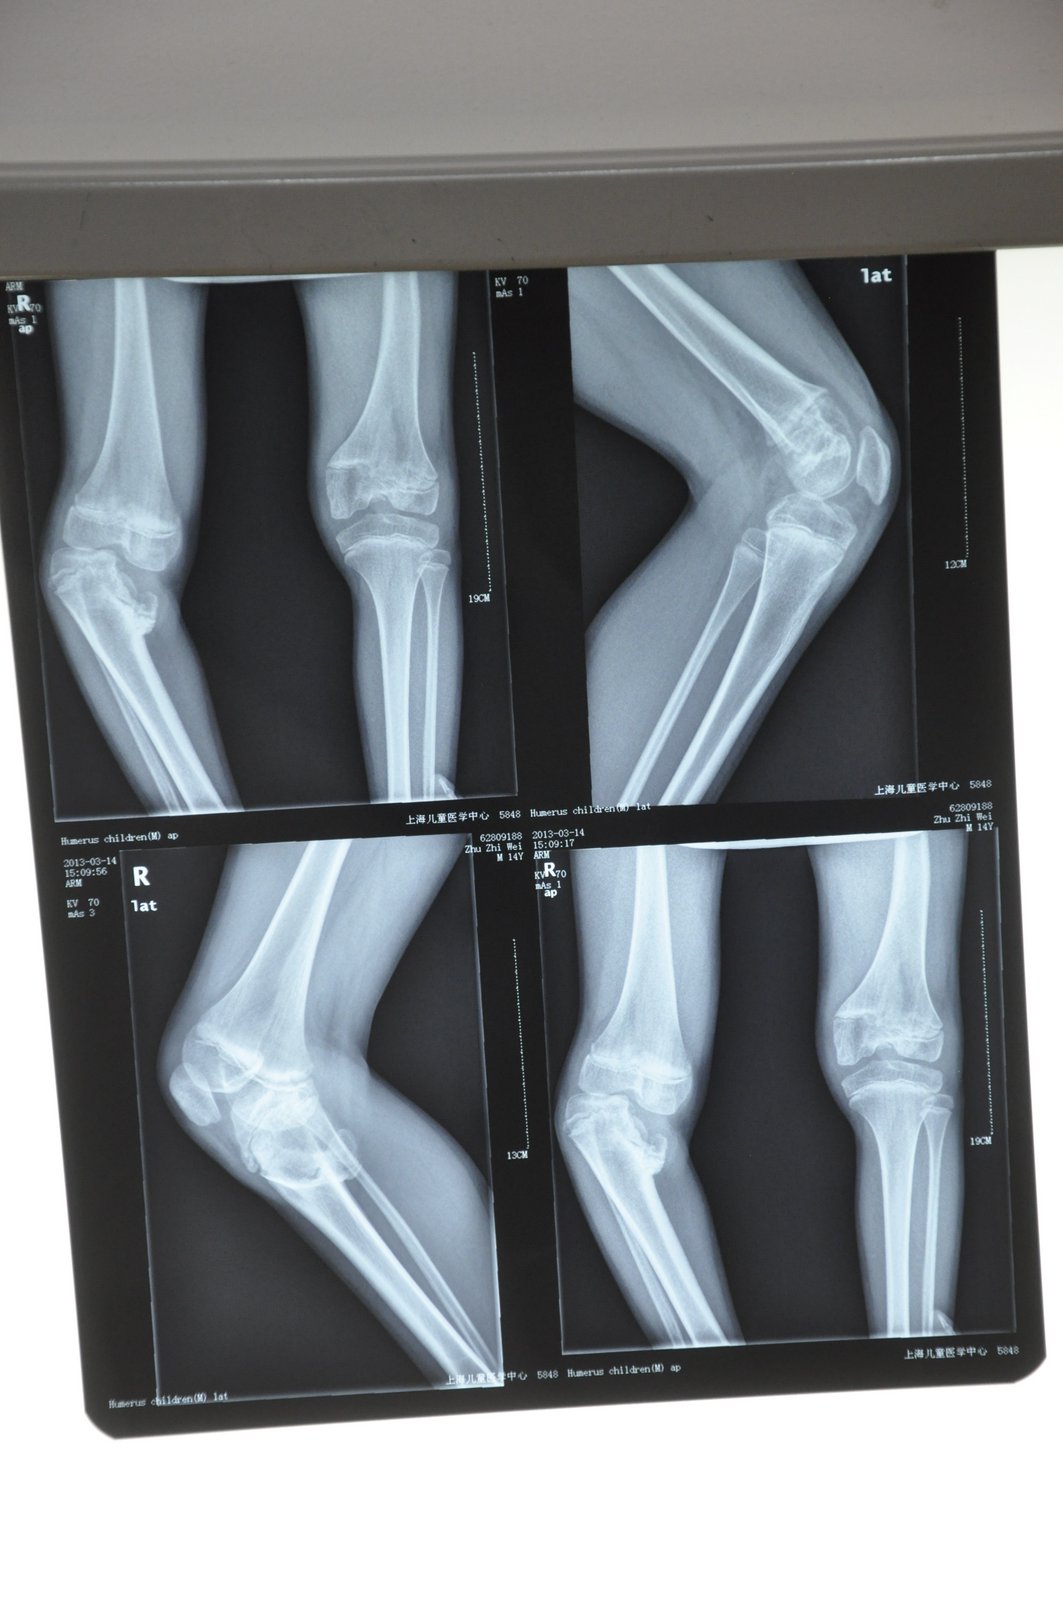

A young 13-year-old boy named Zhiwei (sounds like "Jurway") is about to begin surgery today. I met him and his father on the streets of Shanghai and became friends a few weeks ago when they came to town from the countryside for some big-city medical help. As you can see in the photos below, shared with permission of the family, his leg is badly curved with a severe joint problem. It apparently arose from a serious infection he had as a baby. When he walks, he has to stoop way down with each step on that leg and it looks like it's going to snap. Painful. He had one surgery years ago but it didn't do much. He's getting real help this time. The family, though, has very little money, being poor farmers from Jiangxi province. The surgery will cost about $8,000 (50,000 RMB). I'll be getting details from the hospital today on how people can help if you'd like to donate and help out.

Many thanks to a couple of kind US doctors who gave some free analysis that helped the father decide to avoid a dangerous additional but unnecessary hip surgery that a questionable doctor here had been pushing in addition to the knee surgery. I think the most important part of my role in connecting with these strangers was to help them get vitally needed second opinions here and from kind doctors in the US that helped the father changed his mind and make what I think is the correct decision: knee surgery (only) right now.